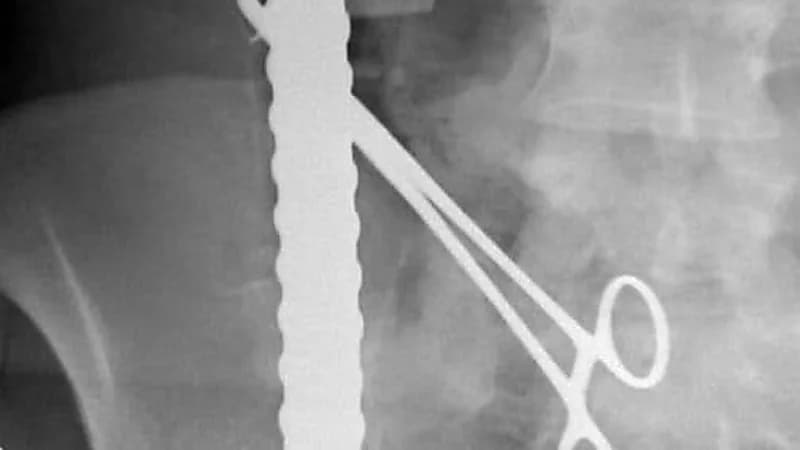

ومن جانبها، أوضحت الدكتورة نورة السبيعي استشاري جراحة الحوادث والإصابات في المدينة الطبية الجامعية الدكتورة، أن المقيم وصل لقسم الطوارئ بعد تعرضه لاختراق 3 أسياخ لجسده واستقرت في أماكن حرجة.

واخترق السيخ الأول الجزء الأيمن من منطقة الفخذ بمحاذاة الشريان والوريد الفخذي، فيما اخترق السيخ الثاني منطقة البطن السفلى تحت السرة.

أما السيخ الثالث فتبين أنه اخترق الحوض من الجهة اليسرى مما أدى إلى كسر مضاعف في تلك الجهة من الحوض واستقر بمحاذاة العمود الفقري دون اختراقه.

وتم استخراج السيخ الأول بعد السيطرة على الشرايين الكبرى، أما السيخين الآخرين فقد تم إزالتهما بعناية شديدة كي لا يؤثر على الأعضاء المحيطة بالمنطقة المصابة مع ترميم الأعضاء المتأثرة جراء هذه الإصابة.